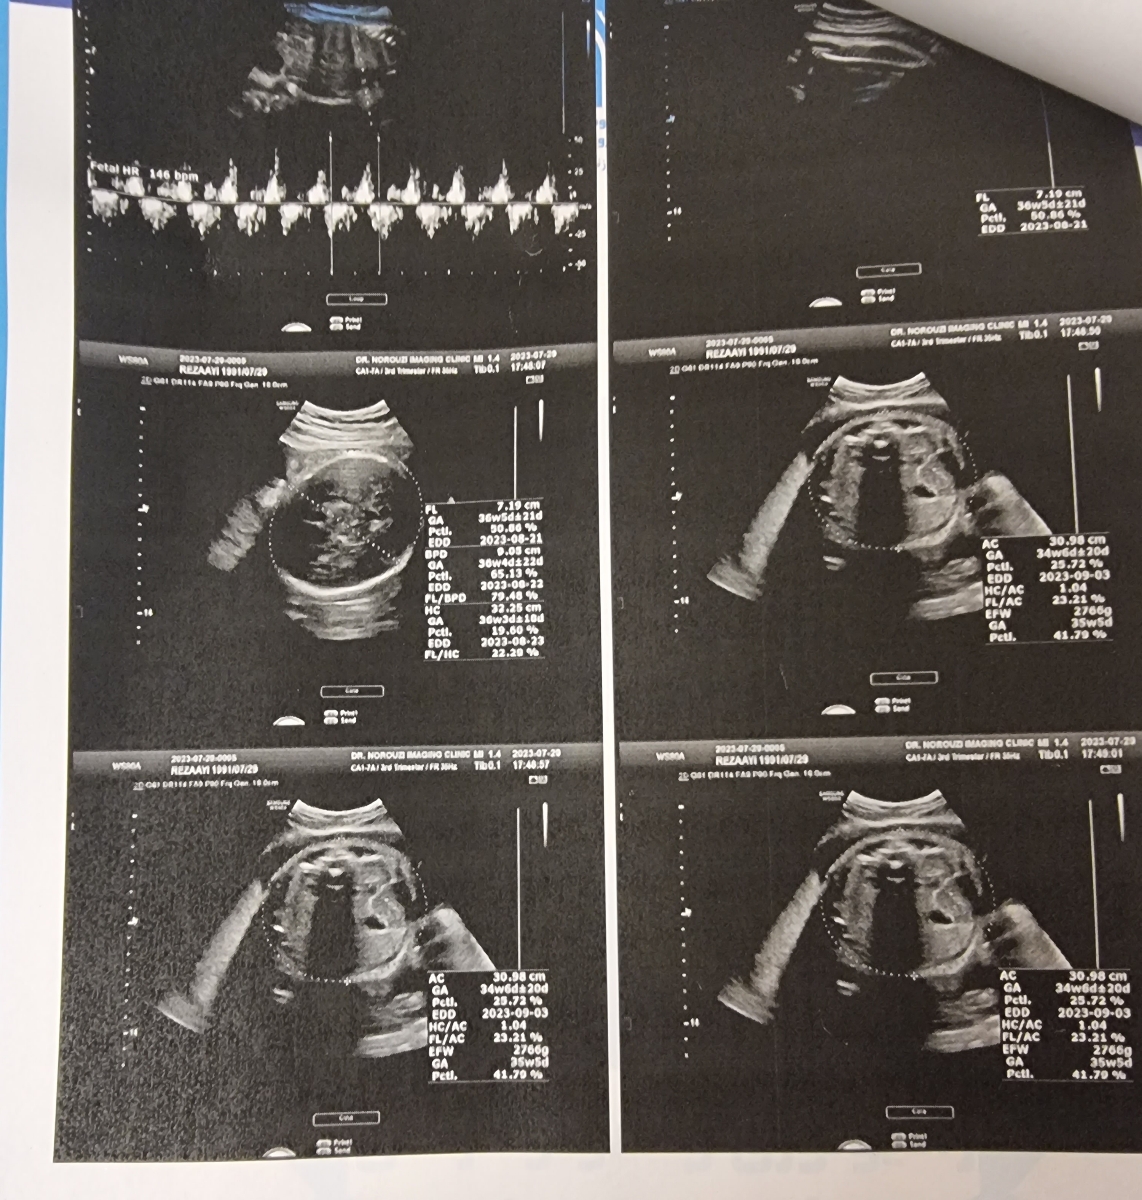

عکس گزارش سونوگرافی را ارسال کنید تا ببینم

خدمتتون ارسال کردم

جان دلم همه چیز خوب است اما دلبندمان باید بیشتر وزن بگیرد، این نکات را رعایت کنید :